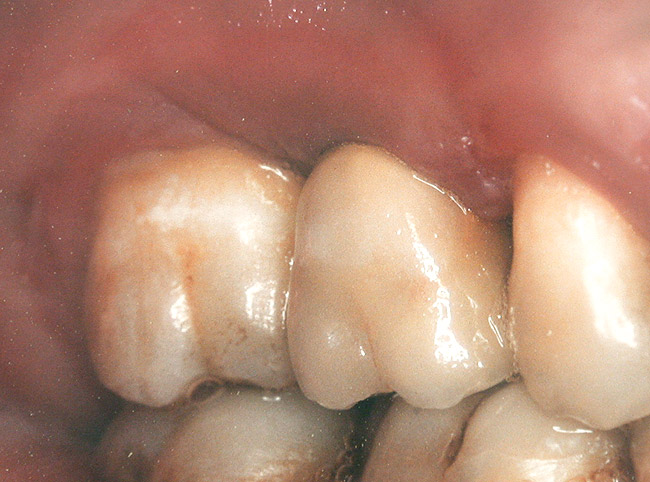

Second-stage surgery was performed after 4 months (Figure 8); healing abutments were placed and the soft tissue was allowed to heal for 5 more weeks. Then, splinted porcelain-fused-metal (PFM) crowns supported by custom gold abutments were delivered (Figure 9 and Figure 10).

Figure 9  Final implant-supported PFM restorations.

Figure 9